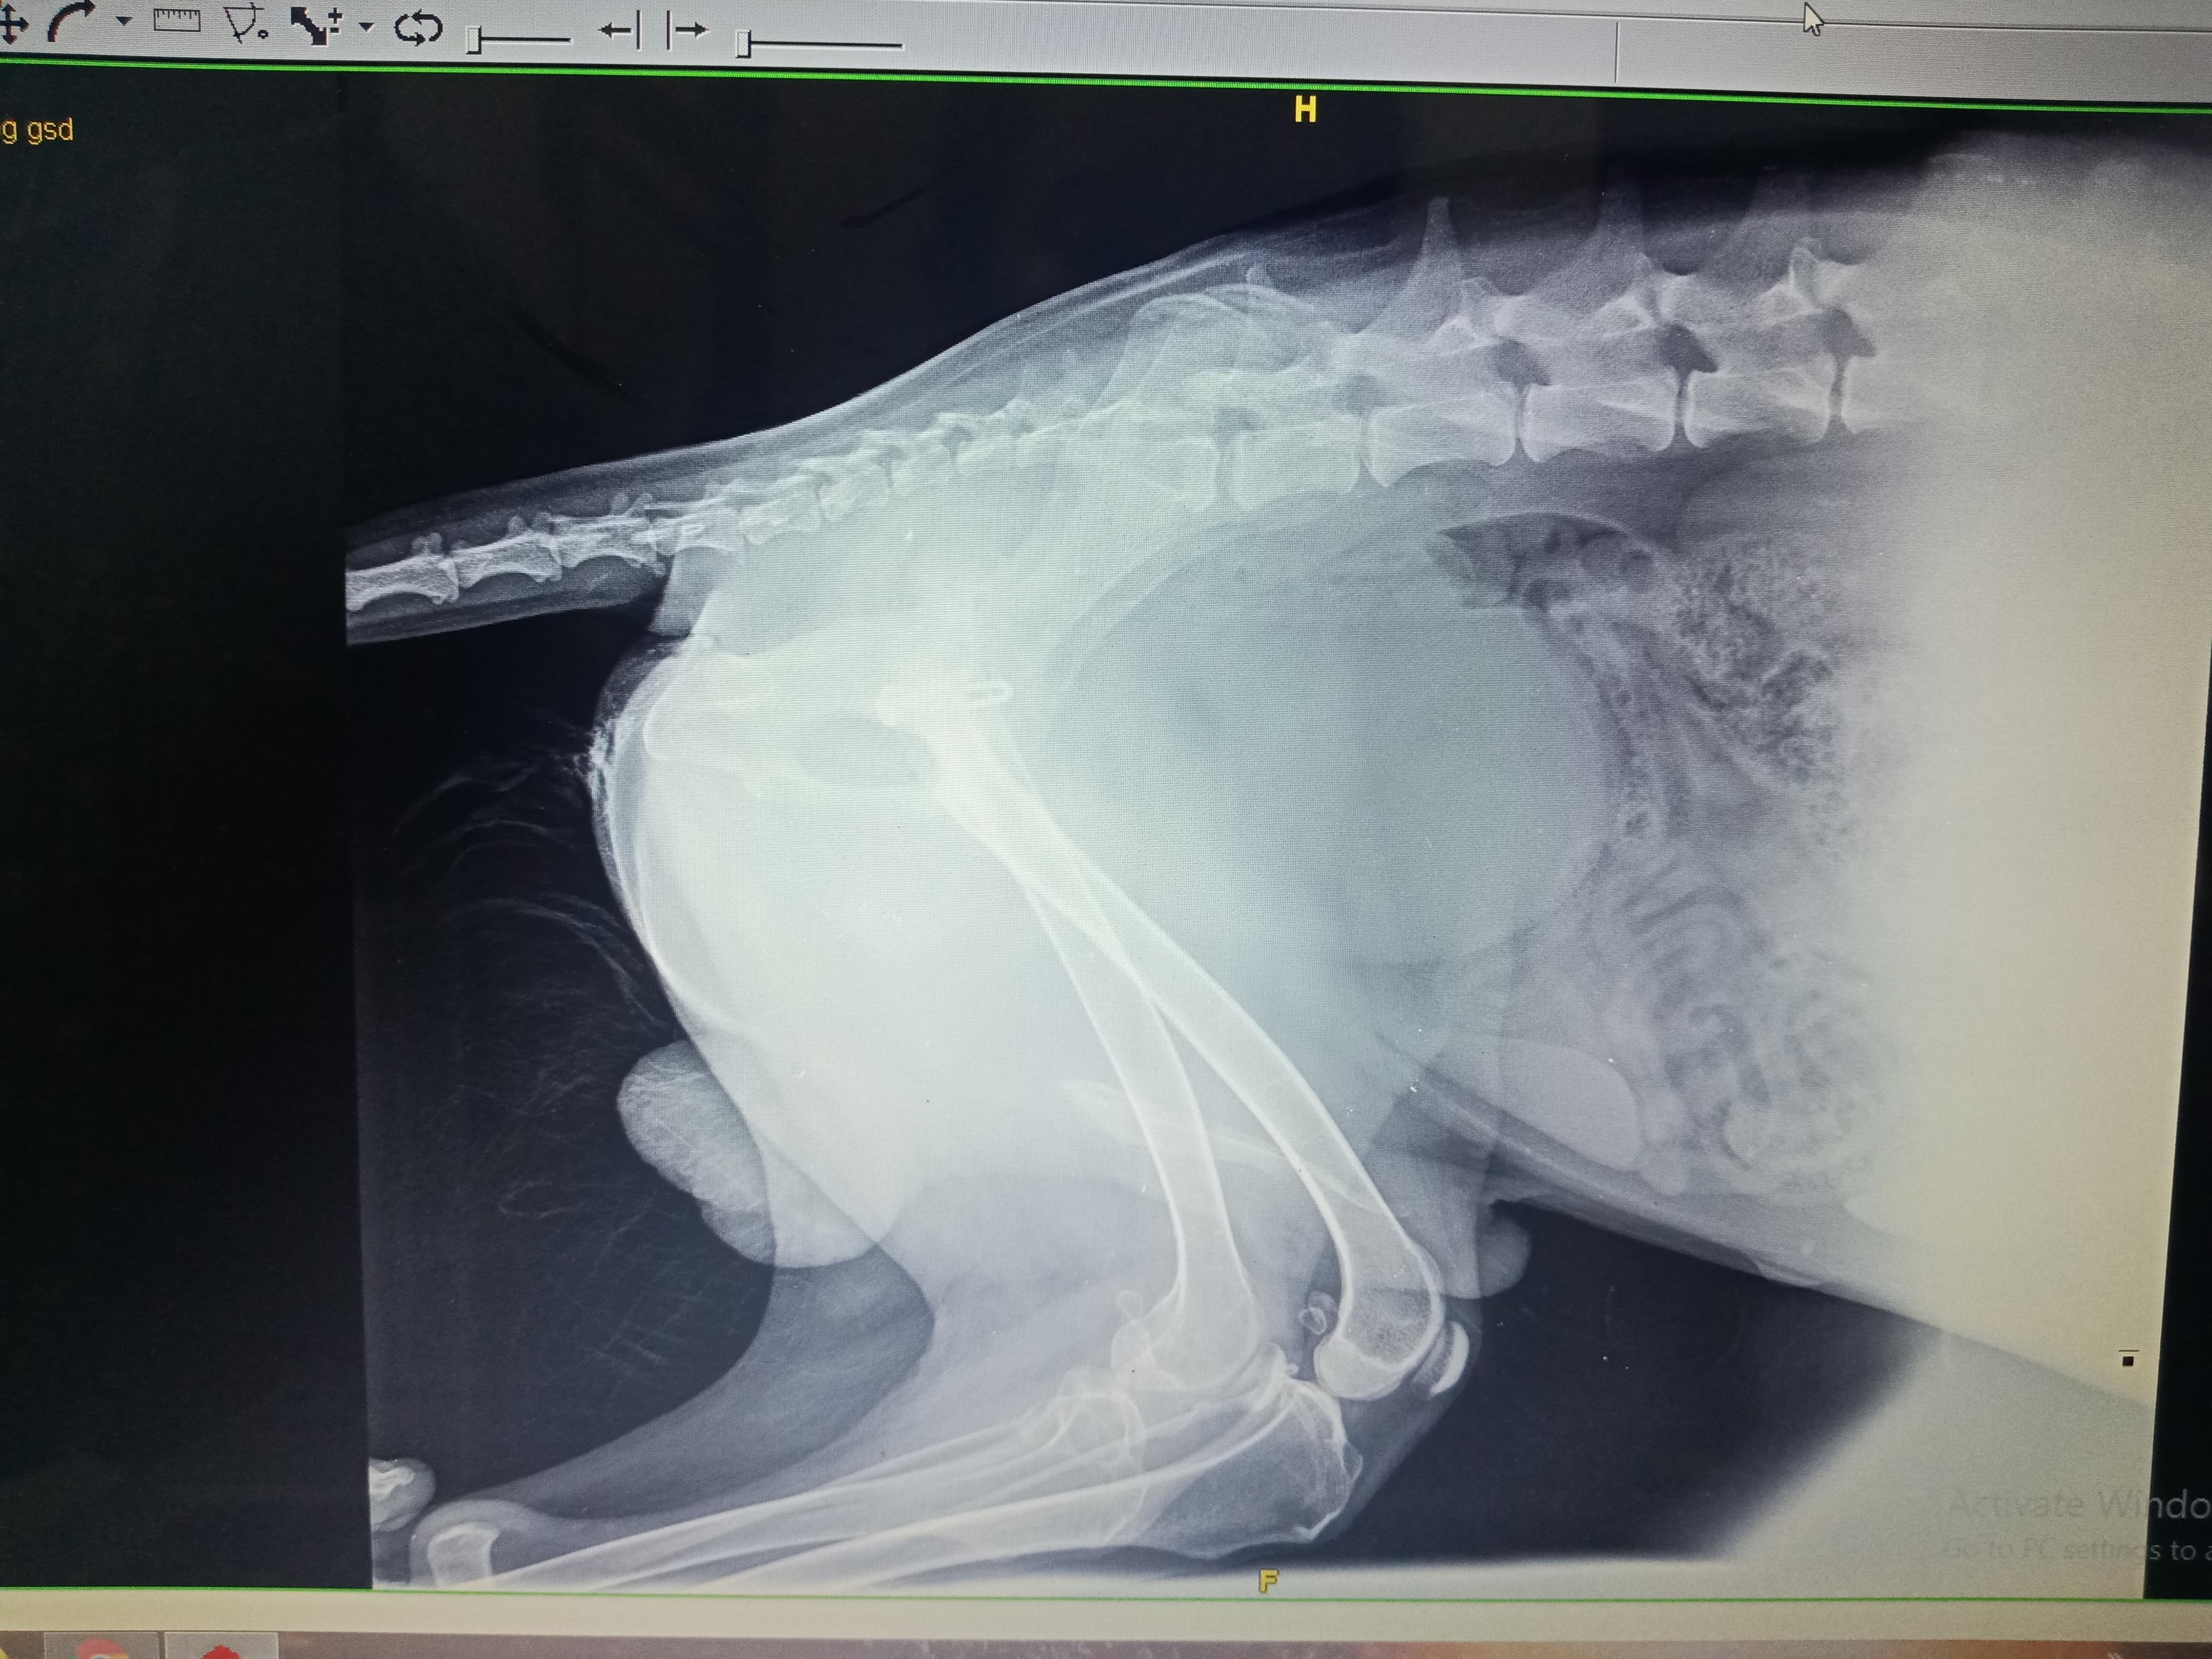

Pet's info: Dog | German Shepherd | Male | unneutered | 11 months and 18 days old | 22 lbs

My German shepherd dog, 11 months old had an accident which led to dislocation of his leg.A surgery was conducted and now after3 months of the surgery the surgical wound was open at a small portion and puss and blood started coming.We used almost all antibiotics and even reopened the wound at hospital.There were signs of infections caused by the screw implanted in his leg. Thus doctor cleaned the puss and he was sent home again.But now the puss and blood comes again.what else can be the reasons?

Unfortunately I'd guess that this is an implant failure, and the symptoms may not resolve until the screw is removed. I'd recommend rechecking with your vet to see what they would recommend next. It's possible that a different surgical procedure will need to be performed, or your vet might want to try getting a culture of the wound and a longer course of antibiotics.